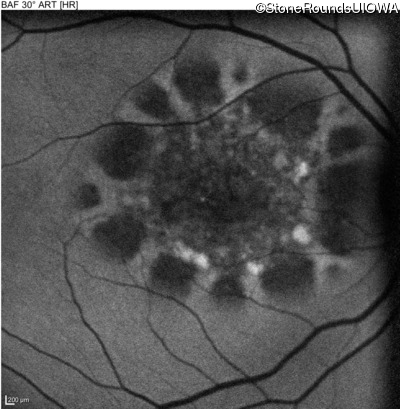

Age at visit: 49 years

This 49 year old man first experienced some mild metamorphopsia at age 35.

Age at visit: 51 years

Age at visit: 52 years